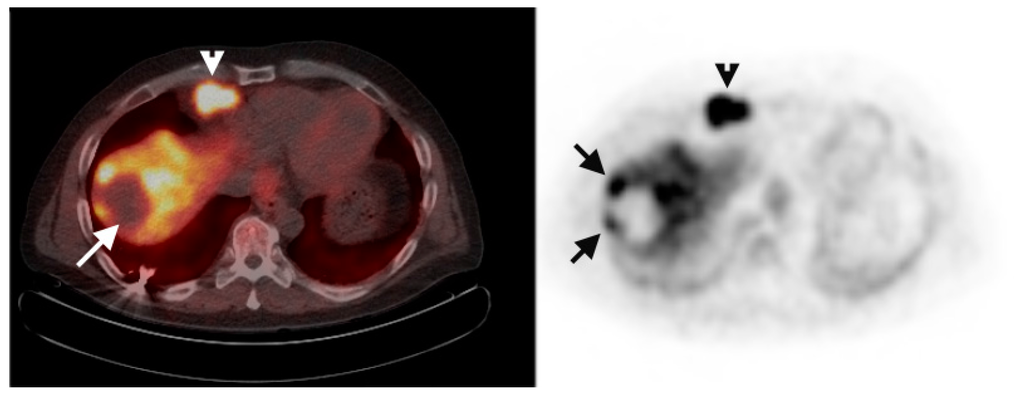

Multiple foci of increased FCh uptake in the liver consistent with multifocal or multinodular HCC (example, Figure 1) were noted in 8 of the 13 patients with increased primary tumor uptake. Of these, the areas of increased FCh uptake were adjacent to the treatment site (examples, Figure 2 and Figure 3) in 2 patients treated by local tumor ablation and 1 patient treated by liver resection. In one newly diagnosed case, PET demonstrated heterogeneous tumor FCh uptake with increased peripheral uptake and markedly diminished central uptake (Figure 4). Pathology in this case revealed a highly-necrotic tumor with Edmondson-Steiner grade 3 differentiation.

Figure 3.

Tumor recurrence near a resection margin. Corresponding PET/CT (left) and PET (right) images of the remnant liver status post partial right hepatectomy shows focal increased FCh uptake (arrow) adjacent to the resection margin. Histology confirmed this lesion as recurrent HCC.